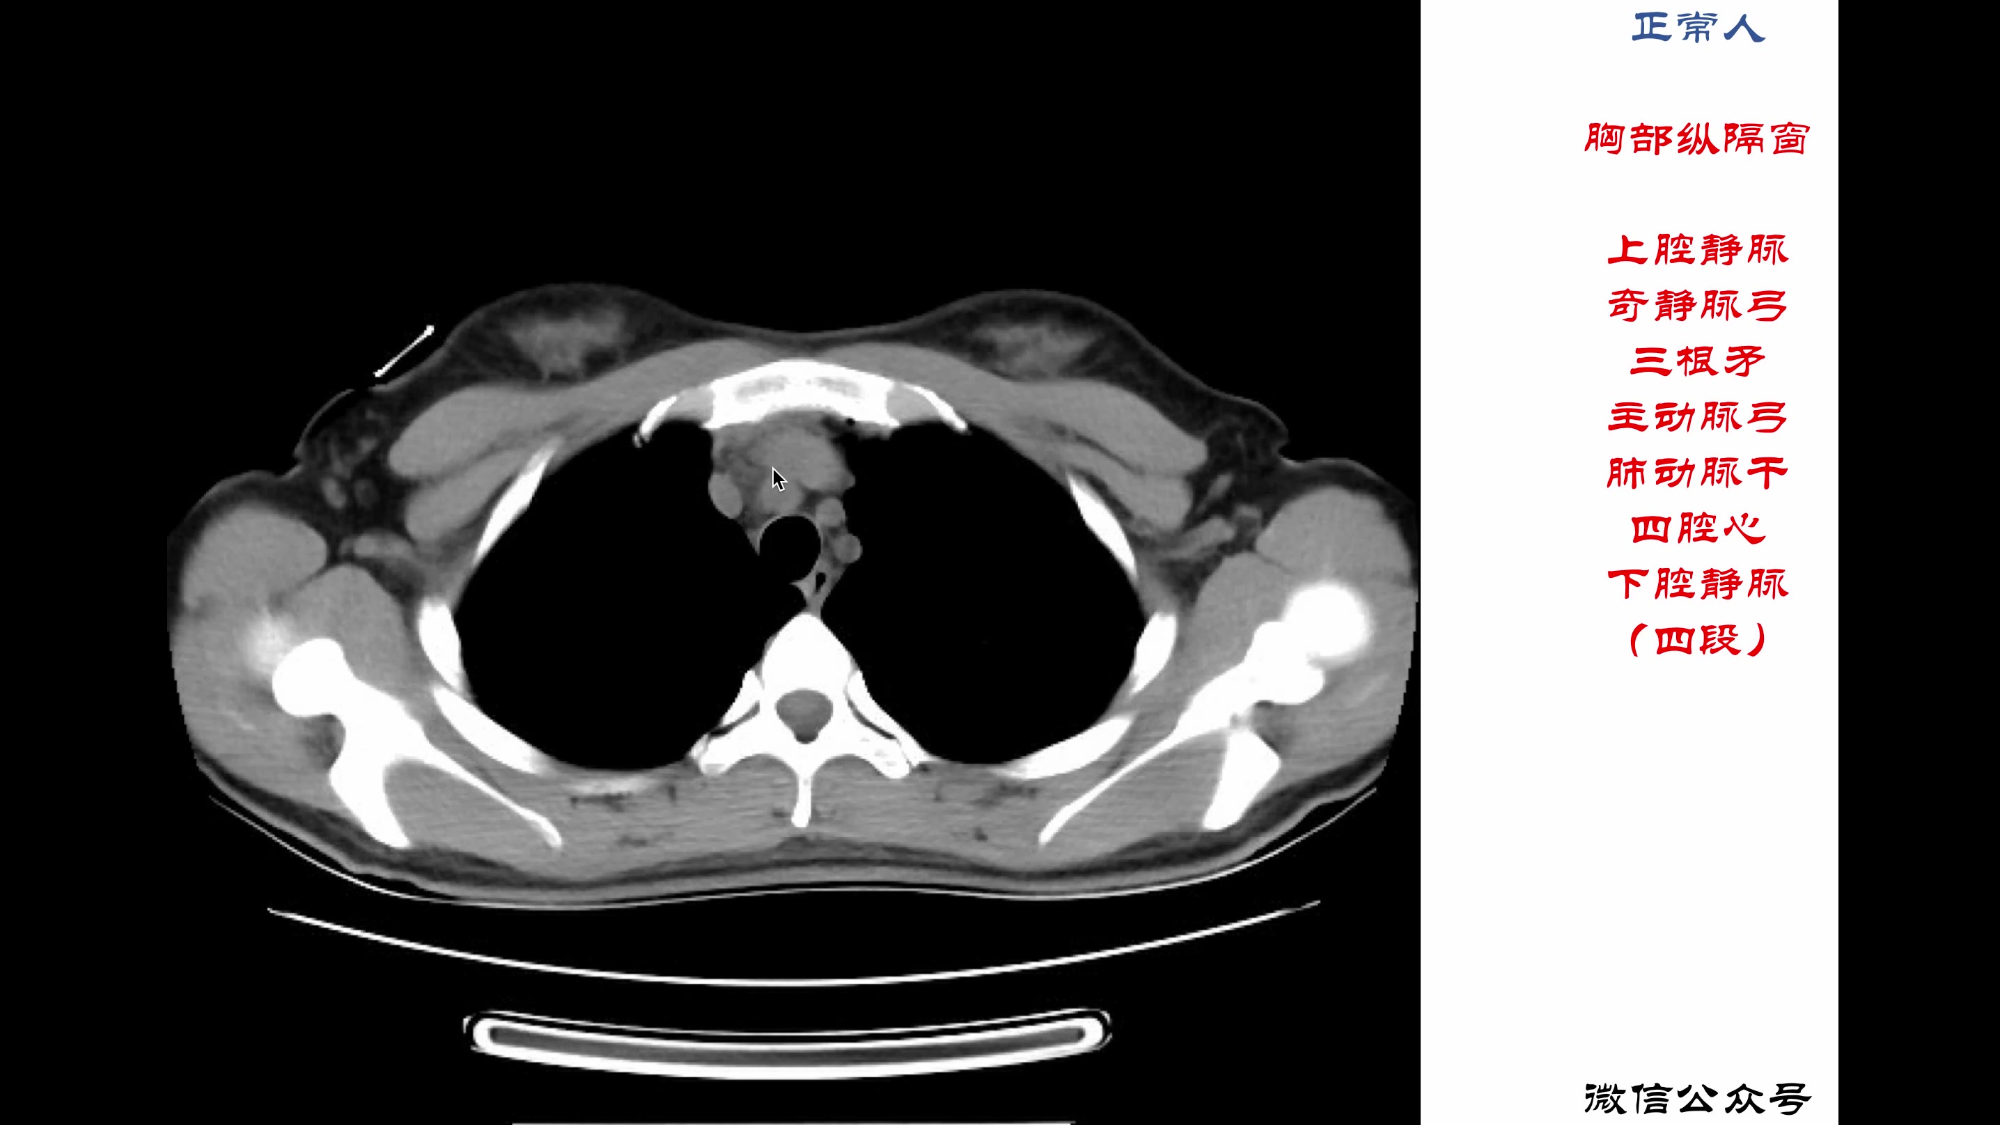

28.肺部CT02

32.怎么看正常胸部CT